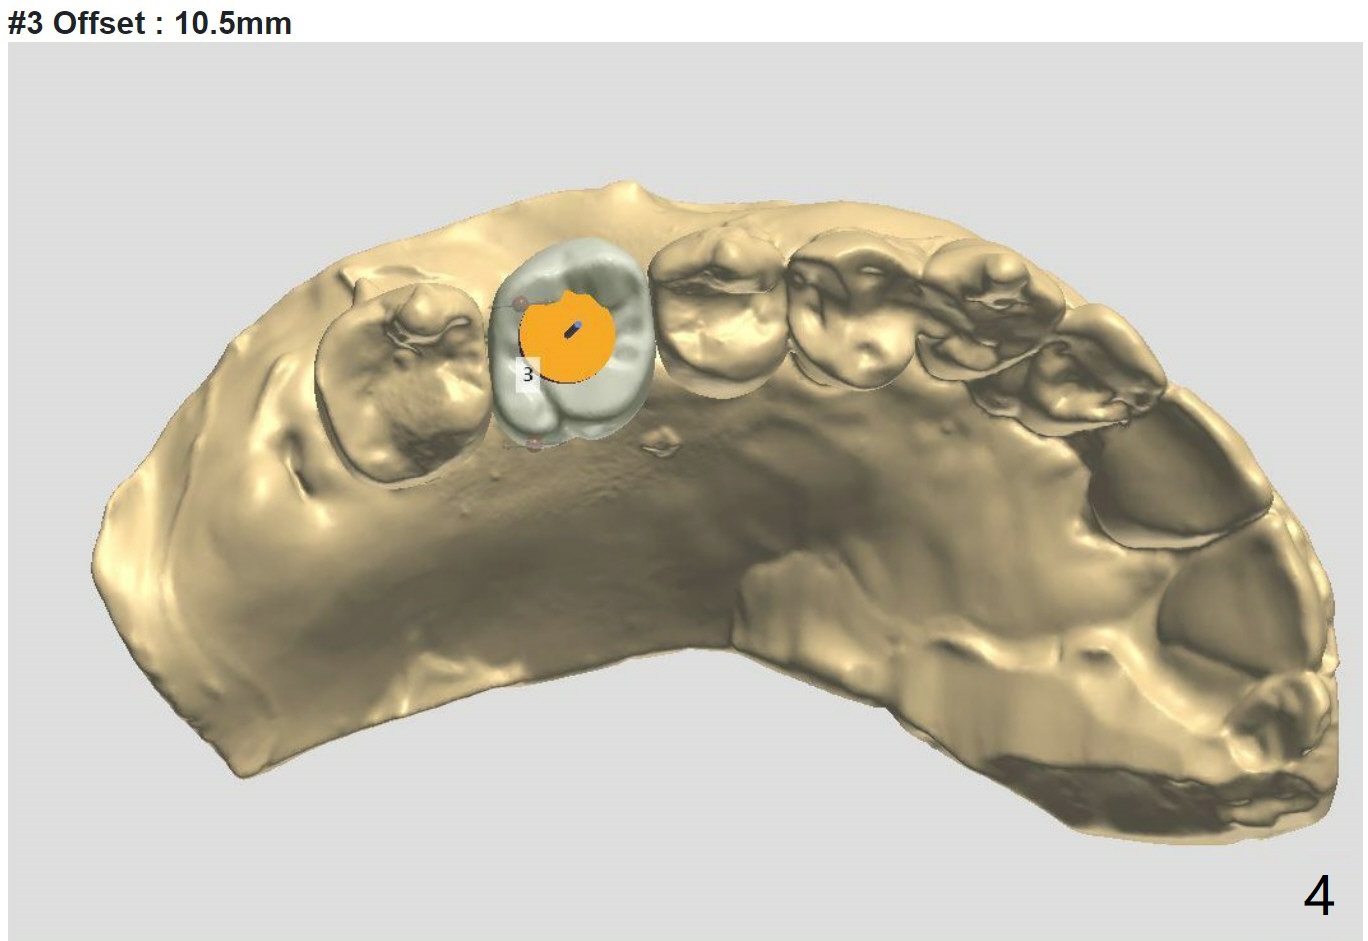

Low Density, Murky Bone Boundary